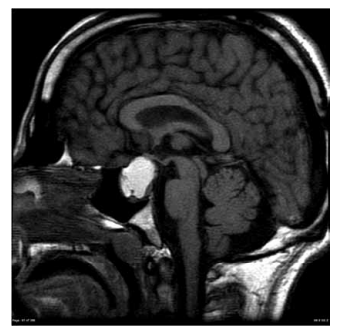

Mulher de 61 anos apresenta quadro de cefaleia progressiva há 5 meses, evoluindo com alteração da visão há 2 semanas. Uma ressonância magnética realizada há 2 dias é mostrada a seguir.

Todavia, ela procura o pronto-socorro devido a mal-estar, sensação de desmaio iminente, náuseas e alguns episódios de vômitos iniciados há cerca de 12 horas. Glicemia capilar: 58 mg/dL. Ao exame físico: afebril, corada, anictérica, sonolenta; pressão arterial: 79 x 46 mmHg, pulso: 82 bpm; frequência respiratória: 20 ipm; oximetria de pulso: normal; discreta dor abdominal difusa, sem sinais de peritonismo; extremidades frias, com discreta cianose. Além de cristaloides, o tratamento imediato correto é